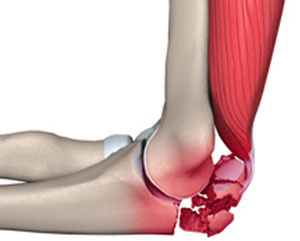

Типичная локализация перелома – локтевой отросток. Он считается самой проксимальной областью локтевой кости. Его можно легко обнаружить при прощупывании поверхности сустава.

Мышцы не защищают отросток, поэтому он подвергается воздействию травмирующих факторов. Перелом может затронуть и мыщелки плечевой кости, шейки лучевой кости и венечный отросток локтевой кости.

Есть разные виды переломов в локтевом суставе:

- незначительное смещение костных отломков, когда не разрывается сухожилие трехглавой мышцы,

- внутрисуставной перелом, когда происходит разрыв сухожилия,

- оскольчатый перелом локтевого отростка.